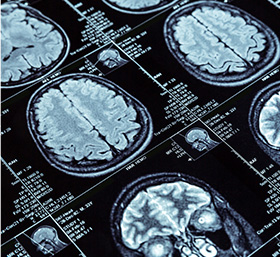

뇌혈관 질환 진단검사

TCD뇌혈류검사

DITI적외선 체열 검사

안진검사

CT/MRI(필요시 의뢰)